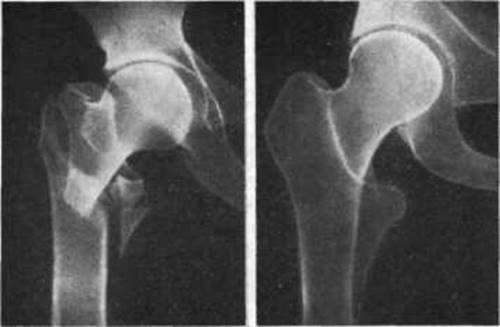

Но окончательно диагноз можно поставить только после рентгена. Снимок, а также обследование врача поможет назначить требуемые процедуры.